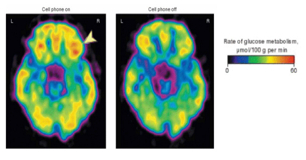

950617_1_3مطالعات زیادی در دنیا وجود دارند که نشان می دهند استفاده از تلفن های همراه خطر ابتلا به سرطان را افزایش می دهد. تلفن های همراه سبب تغییر در مغز می شوند. همچنین نشان داده شده که پس از 50 دقیقه قرارگیری تلفن در کنار گوش در مغز بزرگسالان، تغییرات قابل ملاحظه ای در سوخت و ساز گلوکز در بدن و سوخت گلوکز در مغز مشاهده می شود. تاثیرات طولانی مدت این تغییرات ناشناخته است. تحقیقات اخیر نشان می دهد تلفن های همراه، تلفن های بی سیم و دیگر دستگاه های بی سیم بر روی ریتم طبیعی ضربان قلب تاثیر دارند.